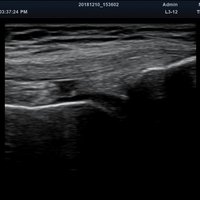

Eigenschaft minisono C1-6 minisono L3-12

Typ konvex linear

Frequenz 1 - 6 MHz 3 - 12 MHz

Maße (Länge/ Breite/ Höhe) 25,5/ 62,5/ 157mm 25,2/ 62,5/ 150mm

Gewicht 5,8 oz/ 175g 5,6 oz/ 165 g

Scan-Tiefe 30 cm 10 cm

Sichtfeld 78 ° 38,4 mm

Display Microsoft Surface Microsoft Surface

Batterielaufzeit 300 min 300 min

Anwendungsbereiche Abdomen MSK, Nerven, Karotis, periphere Gefäße, Schilddrüse, Mamma

Bildgebungs-Modi B-Modus, CF, M, PW, PD B-Modus, CF, M, PW, PD